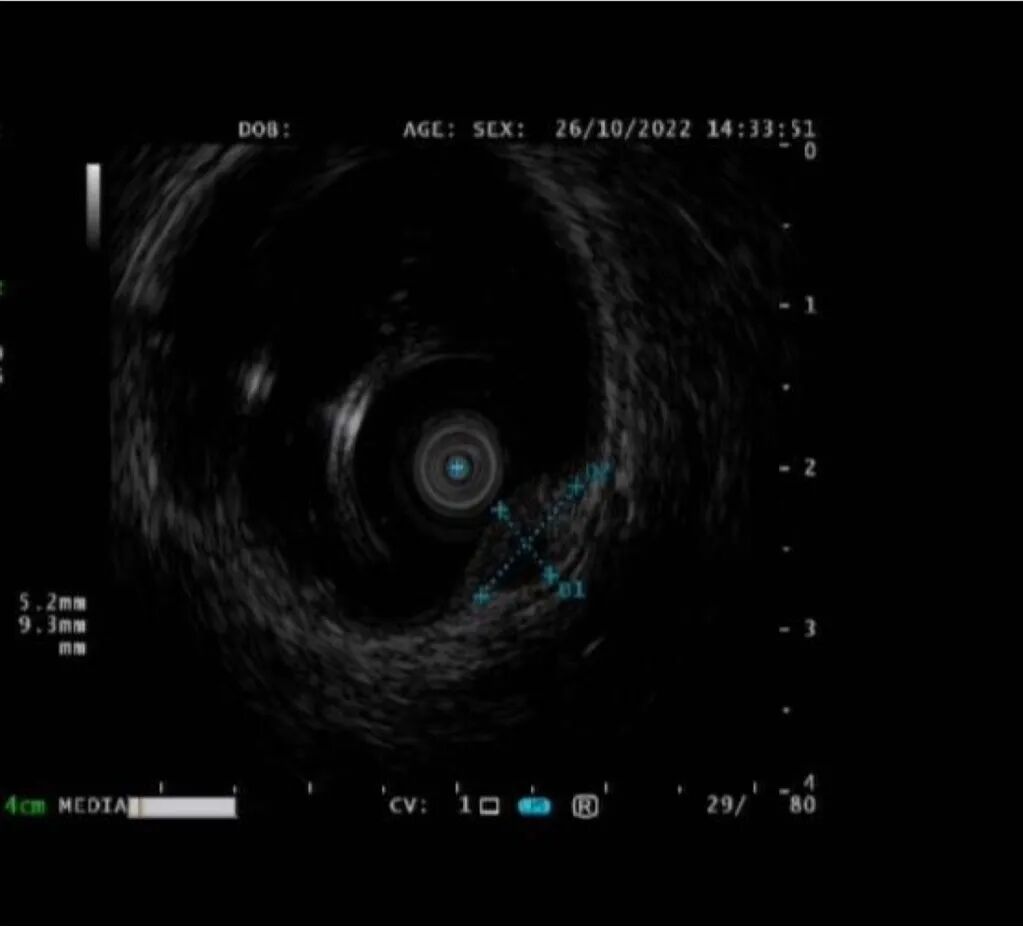

孙某某,女,65岁,因间断上腹痛10余天完善胃镜检查,胃体上段见两处直径0.5-0.8cm黏膜下隆起,超声内镜见病变起源于固有肌层,呈低回声改变,截面大小5.5*6.0mm。

考虑间质瘤,因有增大并恶变的风险,与患者家属详细沟通、解释病情,完成充分的术前评估及准备后,孙院长实施内镜下胃全层切除术,成功将病灶切除;术后病理诊断示“胃间质瘤,患者康复出院”。